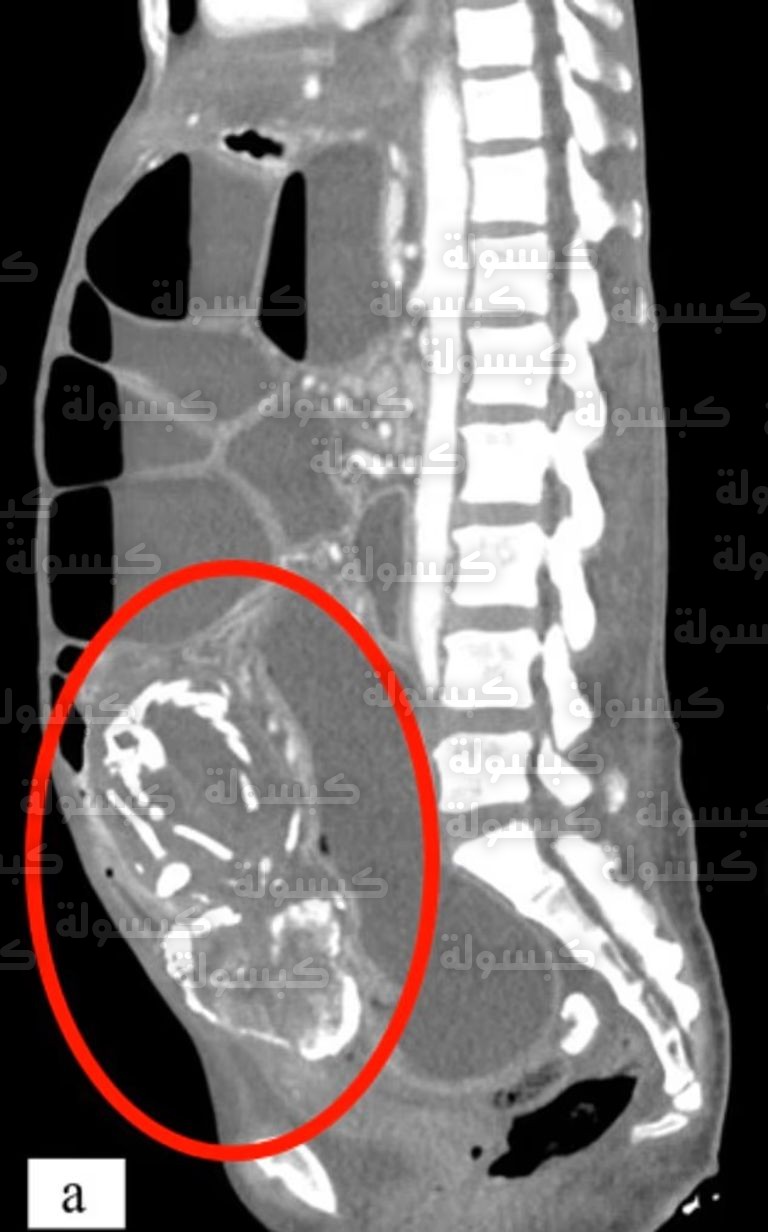

تُعرف هذه الحالة طبياً باسم “لايثوبديان Lithopedion”، وهي اضطراب نادر جداً يحدث نتيجة مضاعفات الحمل خارج الرحم، عندما يموت الجنين بعد الأسبوع الـ 12 ولا يتمكن جسم الأم من امتصاصه أو التخلص منه نظراً لكبر حجمه، يبدأ الجهاز المناعي بتغليفه بطبقة من الكالسيوم، هذه العملية هي آلية دفاعية لحماية الأم من العدوى أو تسمم الأنسجة، مما يحول الجنين تدريجياً إلى كتلة صلبة تشبه الحجر.